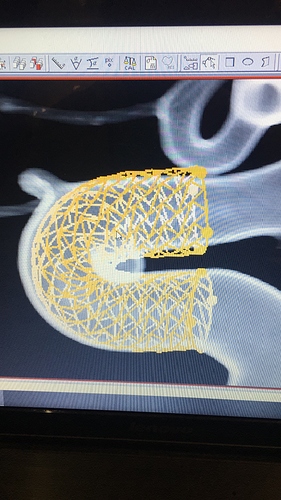

ETA: The names of the flow diverters he mentioned are Surpass and Pipeline

The neurosurgeon did mention that if the annie does not occlude, adding an additional stent inside of the first one would be an option. As I stated above, by that time, Cardiology should be willing to allow me to stop the aspirin and plavix for two weeks prior of doing a clipping or Neurosurgery will leverage the authority to remove me for that prep time.